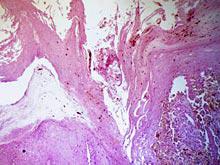

Группа исследователей нашла энзим, который вполне подходит на роль главного виновника развития аутоиммунных заболеваний. Как отмечает Zee News, активация энзима выглядит для иммунной системы как сигнал тревоги. И данный процесс приводил к развитию двух...